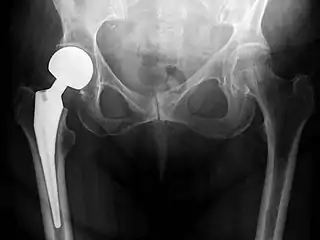

![]() An X-ray showing a left hip (right of image) that has been replaced, with the ball of this ball-and-socket joint replaced by a metal head that is set in the femur and the socket replaced by a cup | |